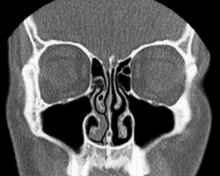

Носовий цикл — явище періодичного набухання носових раковин без зовнішнього подразнення. Процес спостерігається у близька 80% населення та відповідає за відновлення слизової оболонки носа.[1] Регулюється гіпоталамусом.[2]

Ненабухший (вільний) стан називається робочою фазою. У робочій фазі через носову порожнину проходить багато повітря. Виникає підвищена турбуленція, так що повітря, що вдихається, краще зволожується.

При набуханні однієї із сторін виникає фаза спокою. У фазі спокою через носову порожнину проходить менше повітря, і турбуленція зменшується. Через це зменшується також контакт вдихуваного повітря із слизовою оболонкою, яка у той час набирається тепла та вологи.[1]